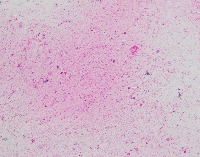

Medical Diagnostics: geckler5 can be used in healthcare facilities to analyze images of tissue samples, blood smear slides, or other medical images to detect the presence and distribution of White Blood Cells (WBC) and Erythrocyte Hemoglobin Concentration (EHC). This can aid in diagnosing diseases such as infections, anemia, or leukemia.

Research and Development: Scientists working in the field of hematology or immunology can use geckler5 to analyze large datasets of blood samples in their research studies. This can help them better understand blood cell morphology, variations, and concentrations in different conditions, ultimately leading to new medical discoveries.

Pharmaceutical Testing: The pharmaceutical industry can utilize geckler5 to analyze the effects of new drugs or treatment methods on WBC and EHC levels. This would allow researchers to monitor the efficacy, side effects, and other critical factors for drug trials and approval processes.

Educational Purposes: Educational institutions teaching medical or biological courses can implement geckler5 as a learning tool, helping students to identify and differentiate between various blood components. This can enhance their understanding of blood cell compositions and related medical conditions.

Blood Donation Centers and Blood Banks: geckler5 can be employed to assess the quality of blood donations in terms of WBC and EHC levels. This automated analysis would help staff ensure that donated blood meets necessary standards and is safe for transfusion into patients.